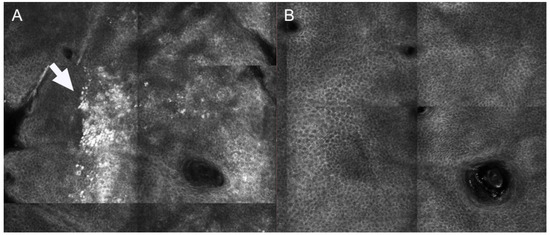

Interestingly, both surgical scars and striae distensae showed parallel collagen fibers, mainly orthogonal to major axis of scar tissue. These parallel collagen fibers were significantly reduced after CO2 laser and PSL for striae distensae [21,22]. Interestingly, a new confocal feature, the “neat wall”, was described at baseline in striae distensae [21], Figure 2. This parameter corresponds to a distortion of the normal DEJ, visible only in RCM mosaic images; it resembles a well-demarcated wall separating regular areas of DEJ, which are formed by round papillae and fibrillar or reticular collagen (definition tab RCM). This parameter was reduced in patients receiving more than 4 CO2 laser sessions, as compared to those receiving ≤4 sessions at 4-week post-treatment [21].

Figure 2. Reflectance confocal microscopy images of a patient with striae distensae at baseline and one month after 5 CO2 laser sessions. (A) At baseline, neat wall feature can be observed (white arrows), with hyper-reflective compact collagen and elongated papillae as well as the presence of an area of regular architecture (white star) (B) After treatment, neat-wall is not detectable and the architecture is predominantly composed of roundish papillae.